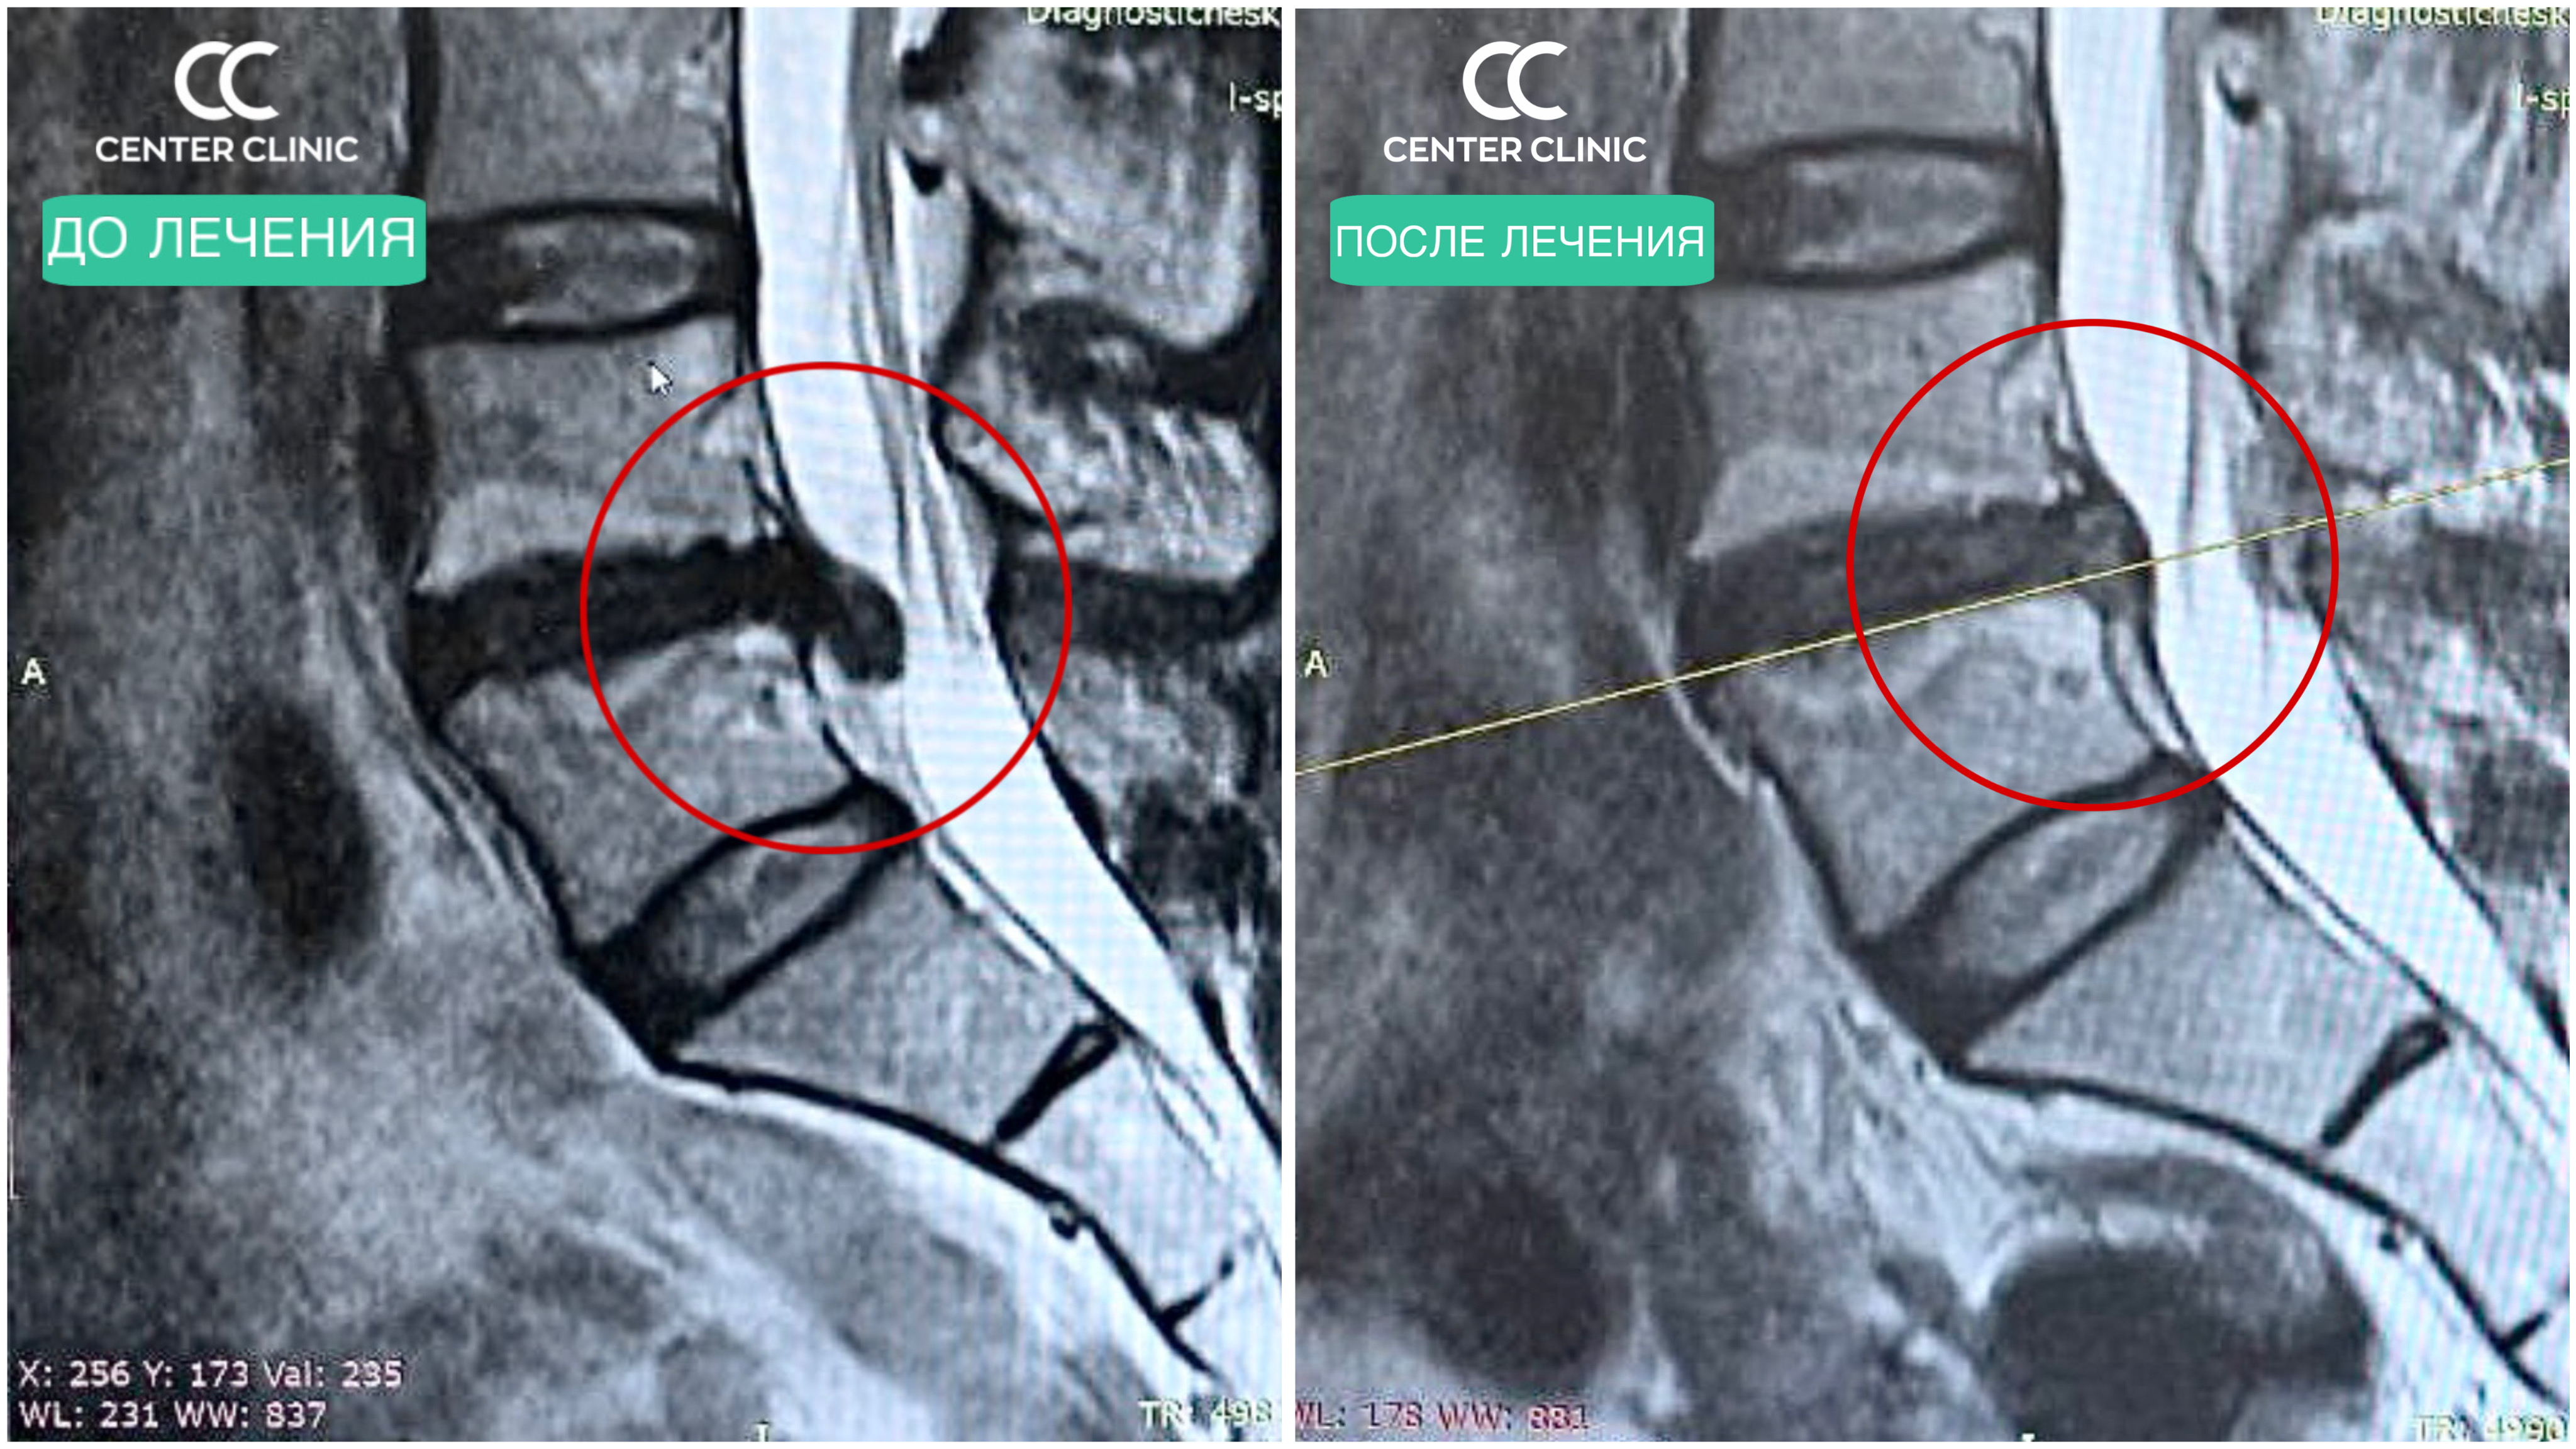

Наш пациент — молодая девушка, 38 лет. Многие годы она жила с болью в спине и ноге, из-за которой пришлось отказаться от привычного ритма жизни. Обезболивающие приносили лишь временное облегчение, а на МРТ — давняя грыжа, с которой, казалось, уже «смирились».

На первичном приёме мы честно обсудили все риски. Перспективы резорбции (рассасывания) такой старой грыжи были, мягко говоря, скептическими. Но вместе мы приняли решение попробовать — шаг за шагом, под контролем и с чётким планом лечения.

И вот результаты:

Клинически — 100% улучшение. Боли в спине и ноге полностью исчезли.

По МРТ — резорбция более 60% грыжи. И процесс продолжается — мы ожидаем ещё лучший результат на следующем контроле.

Честно говоря, этот случай стал приятным удивлением даже для нашей команды: при изначально низких ожиданиях организм ответил на терапию впечатляюще.